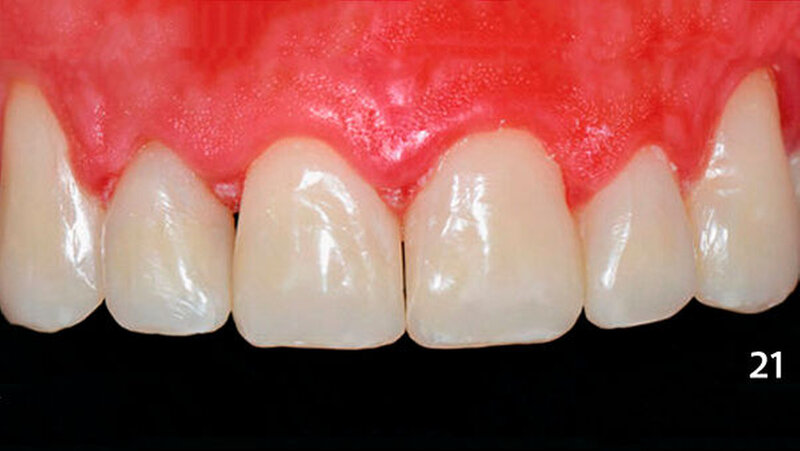

Die Dentinmassen wurden dann von bukkal im inzisalen Anteil mit einer dünnen Schicht Schmelzmasse überschichtet, die im zervikalen Bereich der Zähne mit Bodymasse (Farbe A3B) ergänzt wurde und an diesem Tage aufgrund Zeitmangels nur grob ausgearbeitet wurden. Die Restaurationen stellten sich in der darauffolgenden Sitzung mit oberflächlichen Verfärbungen dar (Abb. 20) und wurden nun vollständig ausgearbeitet und poliert (Abb. 21).